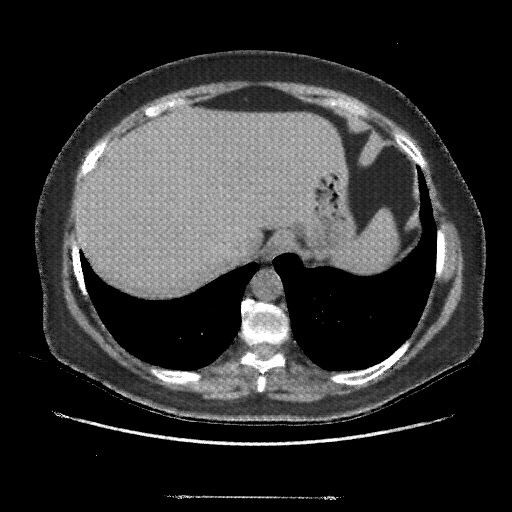

Generated VENOUS CT scan (A→B translation)

Full window (WL 1023.5, WW 4095 β†’ Low βˆ’1024, High +3071)

Actual HU range: [-1024.0, 864.1]

Lung window (WL -600, WW 1500 β†’ Low βˆ’1350, High +150)

Actual HU range: [-1350.0, 150.0]

Mediastinum window (WL 40, WW 400 β†’ Low βˆ’160, High +240)

Actual HU range: [-160.0, 240.0]